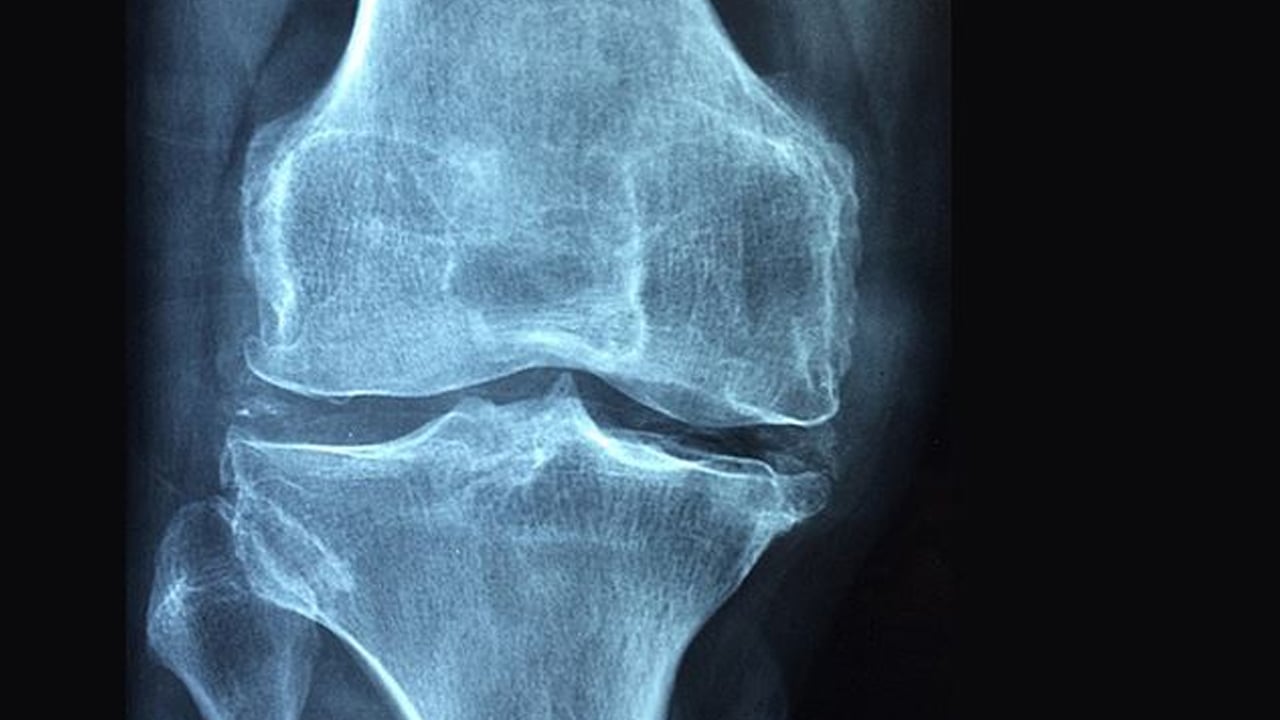

Kemik erimesi olarak bilinen Osteoporoz yatağa mahkum ediyor! Kemik erimesine karşı 7 etkili öneri

20 Ekim Dünya Osteoporoz (Kemik erimesi) Günü bu yıl "Artık kabul edilemez!" temasıyla kutlanıyor. Uluslararası Osteoporoz Vakfı'nın (IOF) vurguladığı bu tema kırıkların; önlenebilir, ancak çoğunlukla göz ardı edilen bir halk sağlığı krizi olduğuna dikkat çekiyor.Kemik erimesi olarak bilinen Osteoporoz hakkında . Bağcılar Eğitim ve Araştırma Hastanesi Başhekim Yardımcısı Fizik Tedavi Uzmanı Dr. İbrahim Ethem Kirez, osteoporoz yani kemik erimesi hastalığının oluşturduğu risklere dikkat çekerek, önemli bilgiler verdi.

KADINLARIN ÜÇTE BİRİ PENÇESİNDE! Uzm. Dr. Kirez, "Osteoporoz sessiz ilerleyen bir hastalıktır çünkü sanılanın aksine kemik erimesine bağlı ağrı genellikle kırık gelişmeden oluşmaz. Dünya çapında 50 yaş üstü kadınların üçte biri, erkeklerin ise beşte biri yaşamları boyunca osteoporotik kırık geçiriyor" dedi. ÖLÜM RİSKİNİ ARTIRABİLİR Kırıkların sadece hareket kabiliyetini azaltmakla kalmadığını, yaşam kalitesini düşürdüğünü ve uzun süreli bakım ihtiyacı gerektirdiğini belirten Uzm. Dr. Kirez, "Yatağa bağımlı olma ve hatta ölüm riskini artırabiliyor. Uluslararası Osteoporoz Vakfı'nın da vurguladığı gibi kırıkların büyük bölümü önlenebilir. Bu konuda topyekün bir farkındalık ve mücadele şart" diye uyardı. ÜLKEMİZDE ORANLAR YÜKSEK Ülkemizde de yaşlı nüfusun artmasıyla birlikte osteoporoz ve kemik kırık oranlarının yüksek seyrettiğini de belirten Uzm. Dr. Kirez, "Yapılan bazı bilimsel araştırmalarda 50 yaş üstü kadınlarda osteoporoz yaygınlığı ve kalça kırığı riski ülkemizde uluslararası ortalamanın üzerinde seyrediyor. Bu yüzden her aşamada yüksek farkındalık, erken tanı ve kişiye uygun yaklaşımlar önem arz ediyor" dedi. EN SIK KALÇA VE EL BİLEĞİNDE GÖRÜLÜYOR Osteoporoza bağlı kırıkların hafif bir travmayla veya kendiliğinden de gelişebildiğine dikkat çeken Uzm. Dr. Kirez, "En sık omurga, kalça ve el bileğinde kırıklar oluşmaktadır. Kırıklar gelişmeden osteoporozun farkına varmak ve tanı koymak açısından taramalar önem arz etmektedir" dedi. BU KİŞİLER KEMİK TARAMASI YAPTIRMALI UZM. Dr. Kirez, hangi kişilerin osteoporoza karşı risk grubunda olduğunu ise şöyle sıraladı: "Ailesinde osteoporoz ve kemik kırığı öyküsü olan kişiler, şeker hastalığı, tiroit bozuklukları gibi ek hastalıkları olanlar, çok düşük vücut ağırlığına sahip kişiler, sigara ve alkol tüketimi olanlar osteoporoz açısından daha da riskli duruma gelmektedir. Risk faktörleri barındıran menopoz sonrası kadınlar ve 50 yaş üstü erkeklerde kemik taraması önerilmektedir" NASIL KORUNACAĞIZ? UZM. Dr. Kirez, osteoporozdan korunmak için önemleri ise şöyle sıraladı: Öncelikle spor olmazsa olmaz. Yürüyüş, koşu, hafif yoğunlukta direnç antrenmanları ve denge çalışmaları hem kemik sağlığını destekler hem düşme riskini azaltır. Düşme riskini azaltmak ve kırık gelişimini önlemek de önemli. Bunun için evde uygun aydınlatmayı sağlamak, kaymaz halılar kullanmak önemli.

Kemilk erimesi olarak da bilinen osteoporoz, kemik mineral yoğunluğunun azalması sonucu kemiklerin zayıflayarak kırılgan hale gelmesidir. Osteoporozda, kemik dokusu, hacmi ve kalınlığında azalma olur ve bu da kemiklerin zayıflamasına ve daha kolay kırılmasına neden olur. Osteoporoz kemiklerin yoğunluğunun azalması ve kalitesinin bozulması nedeniyle incelmesi, gücünü kaybetmesi ve kırılgan hale gelmesi olarak da tanımlanabilir. Vücut çok fazla kemik kaybettiğinde, kemik oluşumu çok az olduğunda veya her iki durumda birden ortaya çıkabilir. Boyda kısalma, kemiklerin kolay kırılması ve bel ağrısı yaygın görülen kemik erimesi belirtileridir.

Osteoporoz (Kemik Erimesi) Nedir? Osteoporoz, kemiklerin, doku kaybından dolayı kırılgan ve dayanıksız hale gelmesidir. Genellikle hormonal sorunlar, kalsiyum ya da D vitamini eksikliği sonucu gelişen osteoporoz hastalığında, kemiklerdeki mineral yoğunluğunun azalması sonucu kemik kütlesi ve kemikler zayıflar bu da kırılgan hale getirir. Kemikler, güçlü kollajen liflerle birbirine bağlanan, esas olarak kalsiyum tuzları olmak üzere minerallerden oluşan yapılardır. Kemik yapısının bozulması ile vücut sürekli olarak kemik dokusunu emer ve değiştirir. Eski kemik dokusu, osteoklast adı verilen hücreler tarafından parçalanır ve yerini osteoblast adı verilen hücreler tarafından üretilen yeni kemik materyali alır. Osteoporozda yeni kemik oluşumu eski kemiğin vücuttan uzaklaştırılmasına yetişemez ve kemiklerde kırıklar ve bunlara bağlı gelişen sorunlar meydana gelir. Kamburluk, boy ölçüsünde kısalma, en ufak bir kaza veya yaralanma olsa bile kemiklerin kolay kırılması, bel-sırt ağrısı gibi durumlar kemik erimesinin yaygın görülen klinik belirtileridir. Bu belirtiler osteoporoz sorunu yaşayan kişilerde ortaya çıkar ancak kemik erimesi bazen hiçbir semptom göstermeden de ilerleyebilir. Genellikle kadınlar ve 65 yaş üstü kişilerde görülen osteoporoz hastalığı, kemik kalitesini güçlendirmeye yönelik ilaçlar, fizik tedavi uygulamaları gibi tedavi yöntemleri içerir. Kemik kalitesini güçlendirmeye yönelik D vitamini ve kalsiyum içeren besinlerle birlikte takviyeler de osteoporoz tedavisinde etkilidir. Osteoporoz (Kemik Erimesi) Neden Olur? Osteoporoz (kemik erimesi), kemik kütlesinin bozulması sonucu kemiklerin kırılgan hale gelmesiyle meydana gelir. Kemiklerde meydana gelen bu bozukluğa neden olan durumların başında kalsiyum eksikliği gelir. Kalsiyum tuzları ve minerallerden oluşan kemikler, vücutta kalsiyum eksikliği olduğunda kırılmaya başlar. Kalsiyum eksikliğinin yanında cinsiyet, yaşlılık, genetik, sigara, hareketsizlik, menopoz, kronik hastalıklar, hormon seviyeleri ve kullanılan bazı ilaçlar da kemik erimesine yol açar. Halk arasında kemik erimesi ismiyle bilinen osteoporoza neden olan durumlar şunlardır: Kalsiyum düşüklüğü ve D vitamini eksikliği Cinsiyet (Kadınlarda sık görülür) Yaşlılık Genetik Sigara-alkol tüketimi Hareketsizlik Menopoz Kronik hastalıklar Hormon seviyeleri Kullanılan bazı ilaçlar Yeme bozukluğu (Anoreksiya nervoza) Kanser Osteoporoz (Kemik Erimesi) Belirtileri Nelerdir? Osteoporozun yaygın görülen ilk belirtisi ise kemiklerin ani ve kolay bir şekilde kırılmasıdır. Bu kırılma en ufak bir kaza veya yaralanma sırasında bile gerçekleşebilir. Kemiklerin kolay kırılmasıyla birlikte boyda kısalma, kamburluk ve şiddetli bel ve sırt ağrısı da kemik erimesi belirtileri arasındadır.